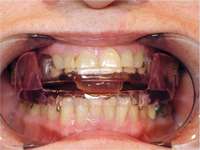

Most often obstructive apnea is a result of more than one site of obstruction.18 Central apnea refers to stoppage of breathing for 10 seconds or longer, not as a result of an obstruction but from the lack of respiratory effort.7 Often when there are central apneas, there are also obstructive apneas, and this condition is referred to as mixed apnea. For a diagnosis of central apnea to be made, 80% of the apnea events must occur centrally.7 Dentists can play a major role in the treatment of obstructive disorders. An understanding of these disorders, the method of action of oral appliances (Figure 6 through Figure 9), and the potential dental and non-dental side effects of these oral appliances will be the focus of the next section.

Figure 6 The SomnoDENT (SomnoMED, Crows Nest, NSW, Australia) is a titratable, custom, durable appliance. The anterior/posterior titration can be readily accomplished by the patient.

Figure 7 The author’s preference is to use appliances with anterior midpoint stops for parafunctional control.

Figure 8 The TAP® III (Comfort Acrylics, Inc, Camas,WA) is a Thornton Anterior Positioner. This version has thermacryl on the interior that allows for easy adaptation with dental changes.

Figure 9 The TAP III is titratable by the patient. Titration of this appliance will control the protrusion of the mandible. Both the TAP and SomnoDENT provide patient-friendly titration, which is extremely helpful as adjustments are made to assure comfort and yet provide adequate muscular tension.